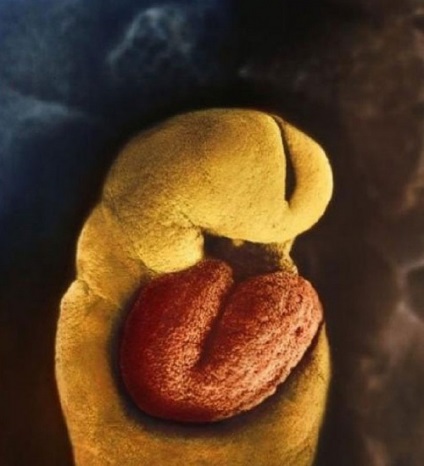

Ziua 22 a dezvoltării embrionare. Materia cenusie - este viitorul creier

In ziua a 18-a embrionului începe inima pulsează

28th zi după fertilizare